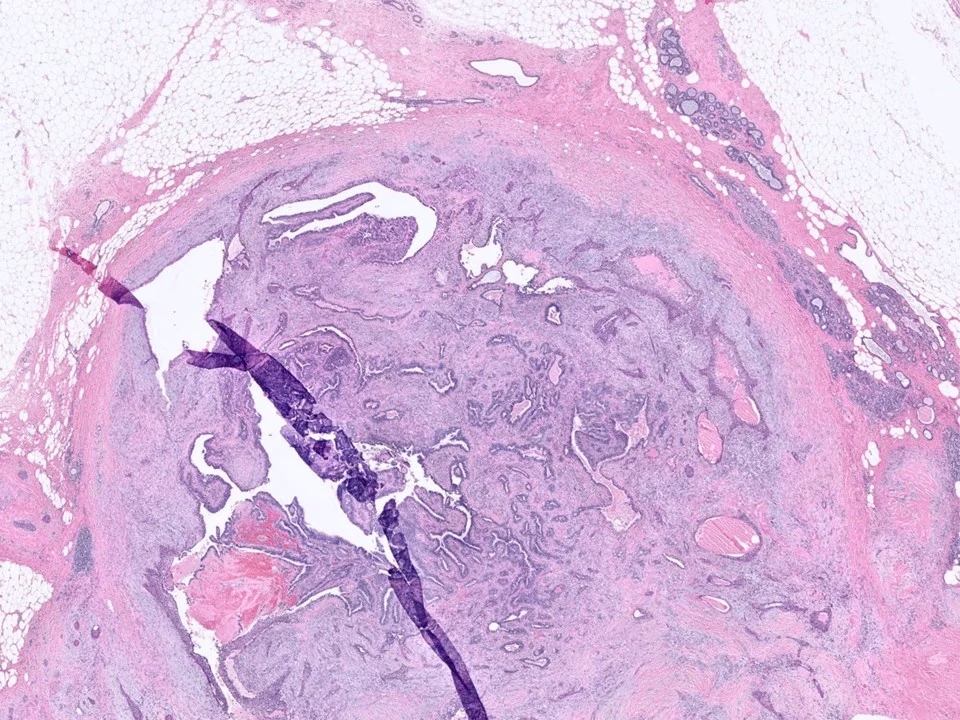

Benign Phyllodes Tumor

Phyllodes tumors are uncommon biphasic lesions that account for <1% of breast tumors. They generally occur in older women as compared to fibroadenomas, and often the patients have a history of a rapidly enlarging tumor. They tend to be larger than fibroadenomas, although this is not a hard and fast rule.

Histologically, phyllodes tumors are characterized by stromal hypercellularity and prominent intracanalicular growth pattern, sometimes with branching, cleft-like spaces.

Malignant Phyllodes Tumor

Frond-like projections of cellular stroma covered by epithelium and myopeithelium protruding into epithelial-lined cystic spaces create a leaf-like appearance.

Malignant phyllodes have an infiltrative border (as pictured here), highly cellular stroma, stromal cells with moderate to marked nuclear pleomorphism, and prominent mitotic activity (>/= 10 mits per 10 HPF)